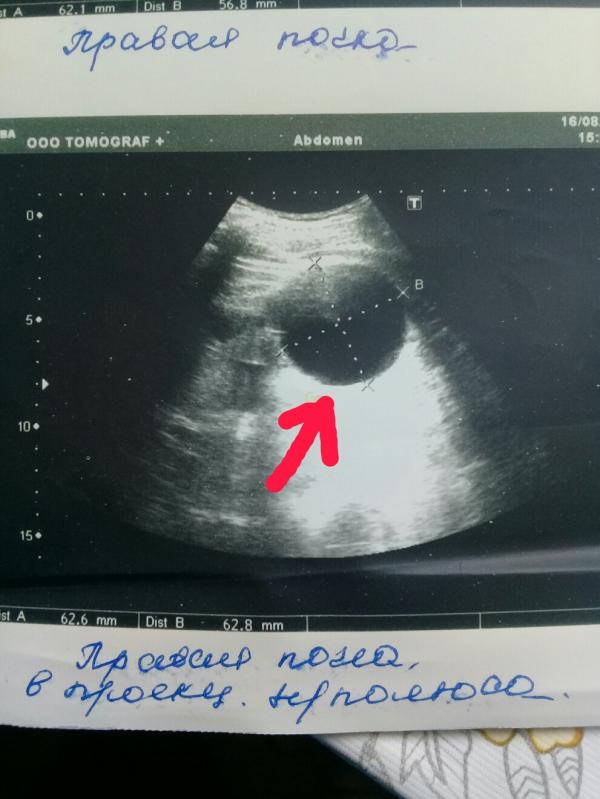

Только в машине я прочитала заключение-ЗНО правой почки. Полезла в интернет, набираю в поисковике ЗНО.... И....все- мой мир рухнул-ЗЛОКАЧЕСТВЕННОЕ НОВООБРАЗОВАНИЕ ПРАВОЙ ПОЧКИ.